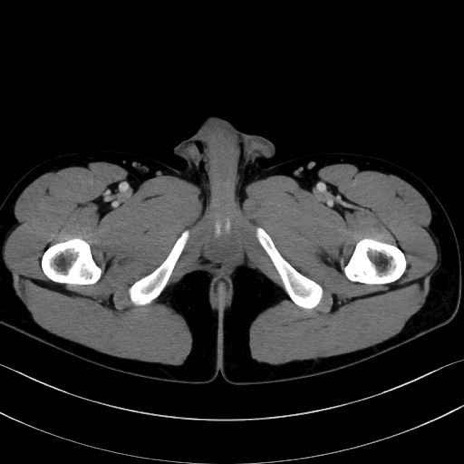

中殿筋 (Gluteus medius)